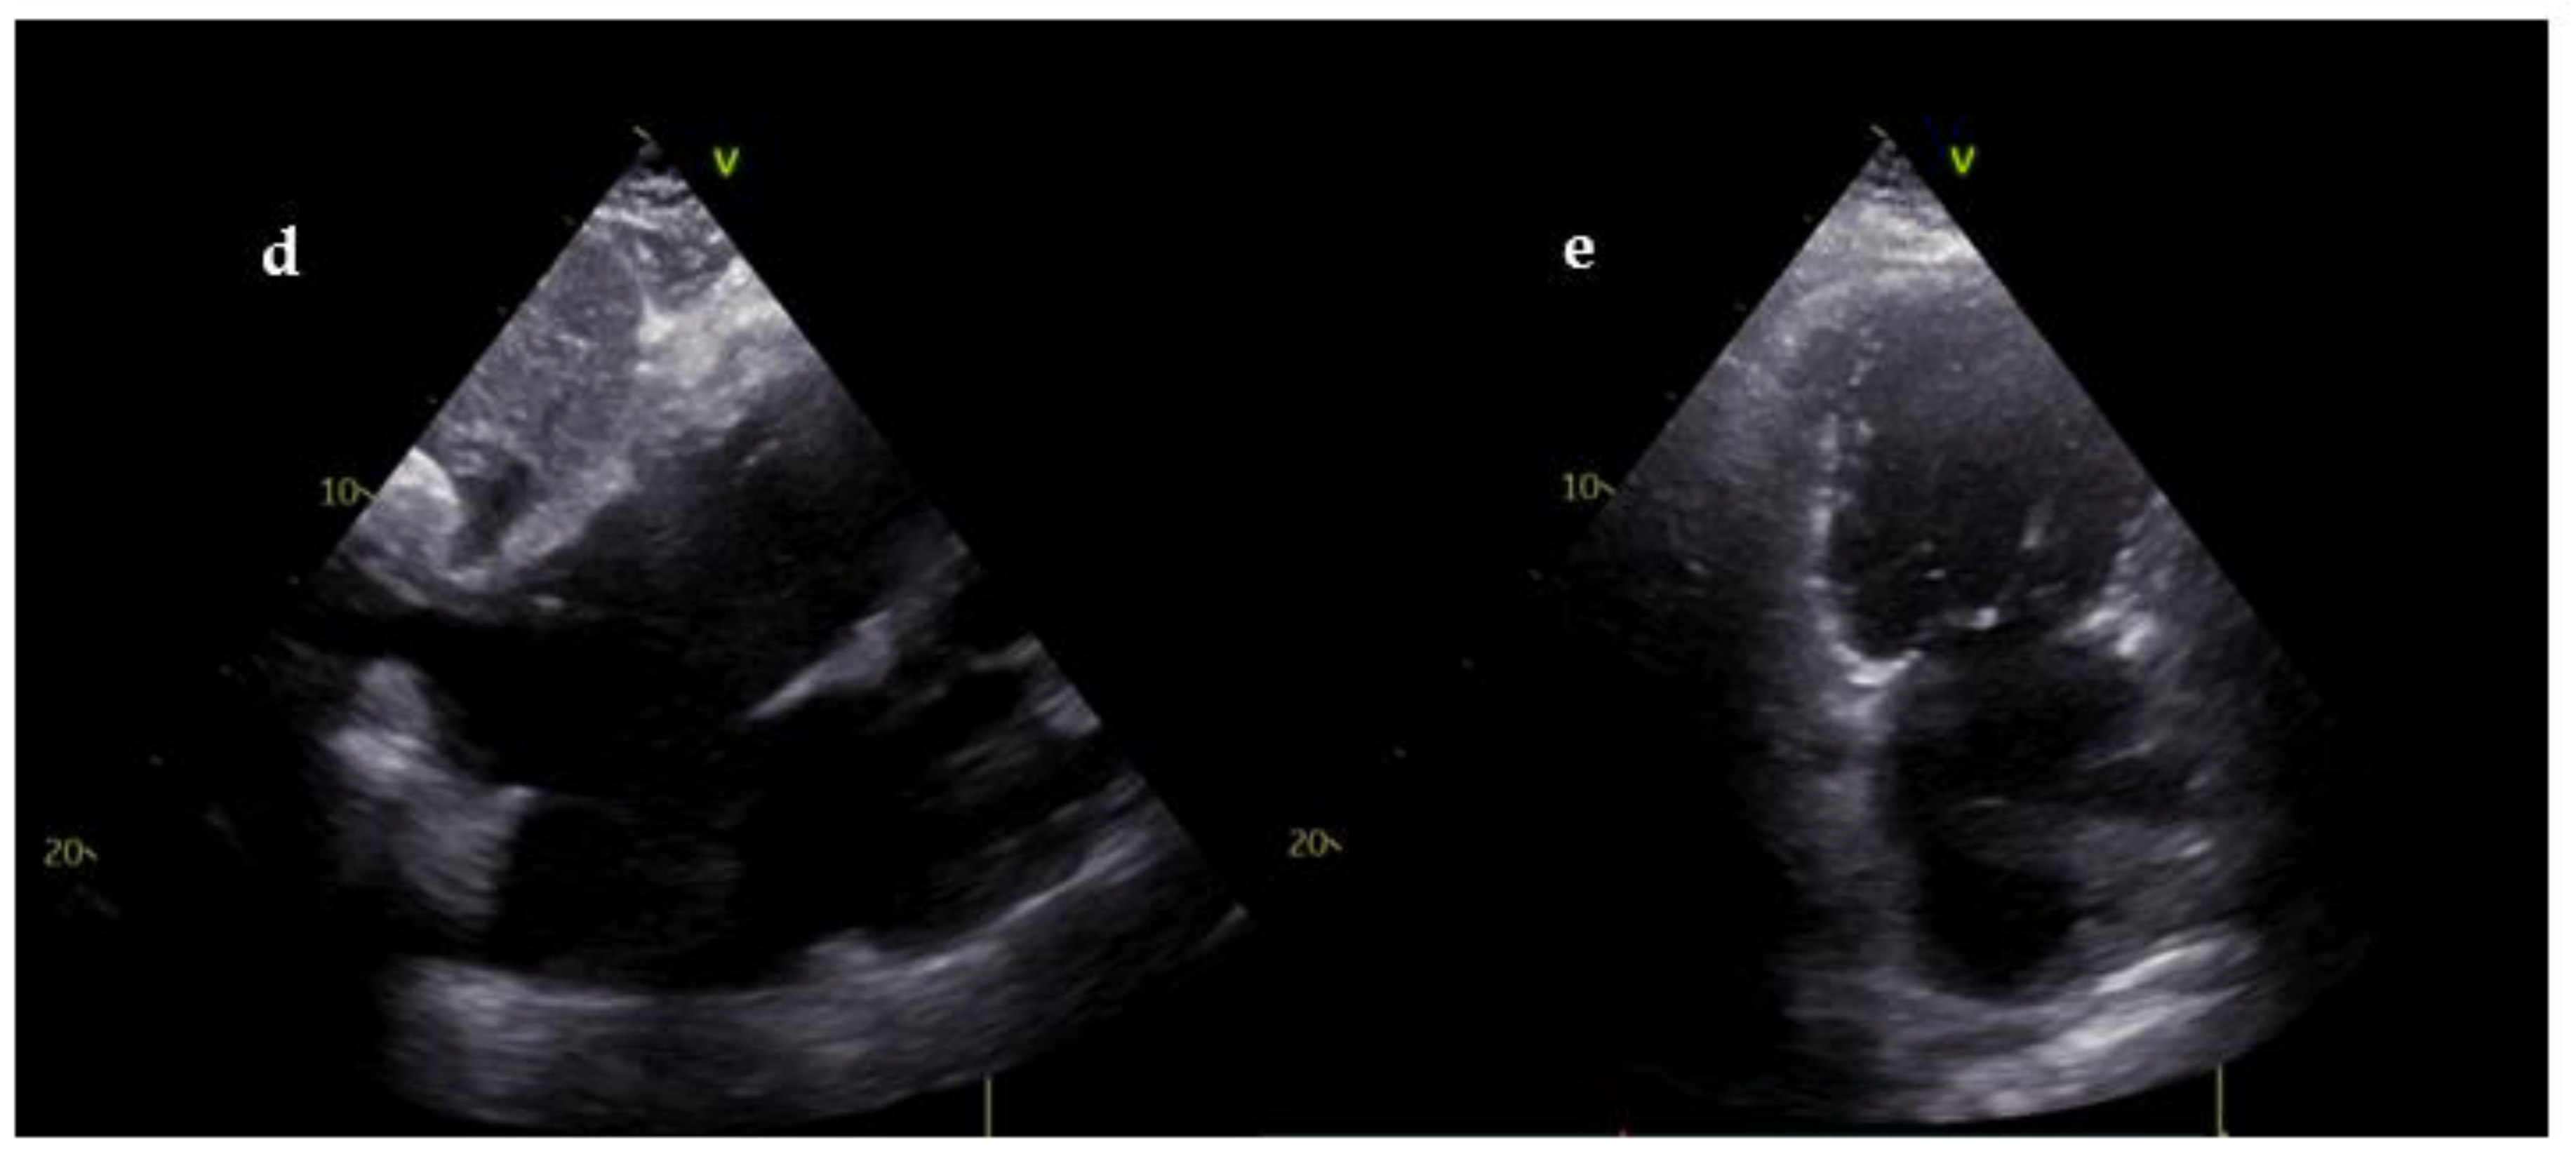

| Echocardiographic findings | Parameters |

|---|---|

| RV dilatation | RV/LV ratio > 1 RV basal diameter > 41 mm RV mid diameter > 35 mm |

| RV systolic disfunction | TAPSE < 17 mm S’ wave (TDI) < 10 cm/sec RV-FAC < 35% RV Tei index (PW) > 0.43 RV Tei index (TDI) > 0.54 RV free wall strain > -20% |

| McConnell Sign | RV basal and mid free wall akinesia and normal motion of the RV apex |

| RV pressure overload | TR Vmax > 2.9 m/sec Pulmonary flow AcT < 60 msec Pulmonary flow mid-systolic notch Paradoxical IVS motion Flattened IVS with D-shaped LV Dilated PA (> 25 mm) TAPSE: PASP ratio < 0.4 Dilated IVC (>21 mm) and/or diminished collapsibility |

| 60/60 Sign | TR jet gradient < 60 mmHg and Pulmonary AcT < 60 ms |

| Thrombus in transit | Thrombus in RV, RA or PA |